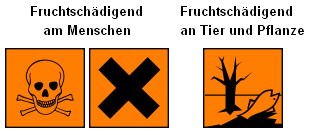

|

Die Symbolde für teratogene, erbgutschädigende

Substanzen wie Quecksilber, gemäss Wikipedia.

Schlimmer gehts es nicht. |